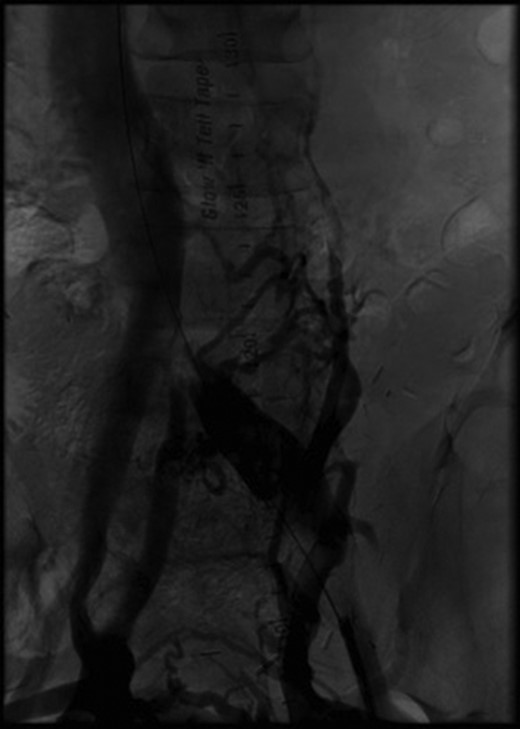

(A) Stent placement (B) Angiography post-thrombectomy and stent showing intact runoff to pancreatic and renal allografts (arrows).

Two months after her transplant she developed abdominal pain and a CT scan was performed. Imaging demonstrated an extensive thrombus in the left common and external iliac veins, with compression of the left common iliac vein superior to the thrombus (Fig. 2). An interventional cardiology team performed angiography which showed a 100% occlusive lesion in the left CIV, with thrombotic defect in the left EIV, and patent pancreatic SMV and left renal vein. Balloon angioplasty and combined Angiojet and manual thrombectomy of the left common and external iliac veins was performed. A 16 mm x 40 mm Wallstent self-expanding metal stent was deployed in the left CIV, with a proximal landing site in the IVC, just distal to the pancreatic vein graft. Post-procedure angiography demonstrated a 30% residual stenosis, with patent flow through the LCIV and LEIV, and both the pancreatic and renal grafts. She was started on therapeutic anticoagulation after the procedure. Surveillance imaging 6-months post-procedure demonstrated no residual clot burden and appropriate stent positioning. Labs at 1 year follow up show persevered allograft function, with creatinine 0.91, amylase 88 and lipase 140, and no insulin requirements.